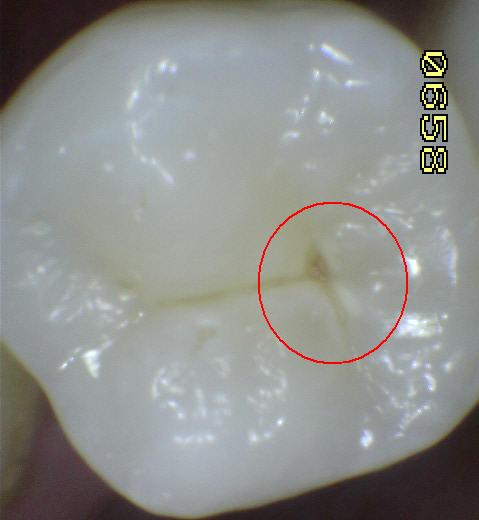

Una morfología de la fisura estrecha, con forma de botella de "Coca-Cola" genera un nicho ecológico ideal para la colonización de cualquier bacteria productora de ácidos. Al no poder remover en forma períodica dicho biofilm de una zona tan estrecha, el ataque ácido genera una lesión cariosa en la dentina, con un aspecto de esmalte intacto a la inspección visual, o sea un típico código 3 y 4 de ICDAS Completo. (Caries Moderada para el ICDAS COMBINADO)

Por este motivo es importante realizar el sellado de las fosas y fisuras de molares y premolares cuando comienza su erupción dentaria, como método de prevención eficaz de caries.

Código 3 (Caries moderada) in vitro. Los códigos 3 in vivo debe ser sellado para evitar el avance del proceso carioso. (MNO)

El diente al lavarse y secarse con la jeringa triple deja expuesto esmalte blanquecino escarchado o opaco que delata un proceso de desmineralización, debido a que el agua se evapora de los microporos. Ver círculos rojos